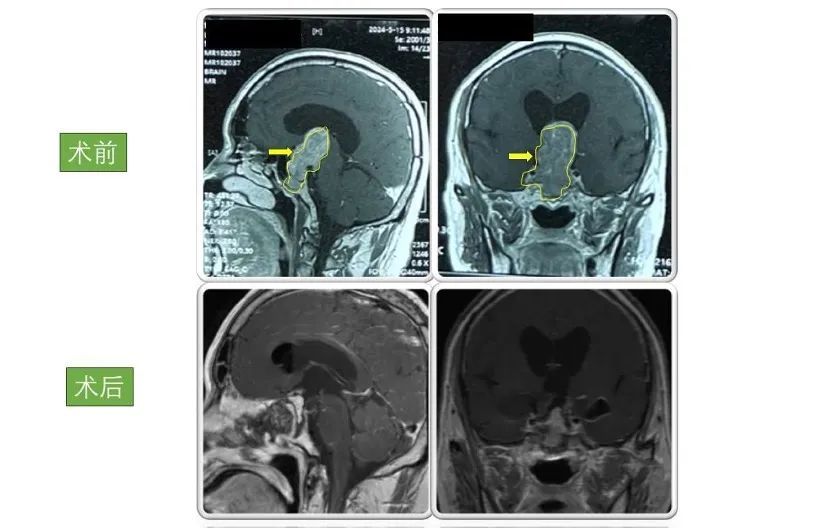

患者3

男性,50岁,因“头晕伴四肢乏力及小便失禁2周”入院。入院检查显示巨大垂体腺瘤,大小为6.5×3×3cm。

术后患者症状好转,小便失禁症状消失,病情稳定后出院,现恢复良好,定期复查。